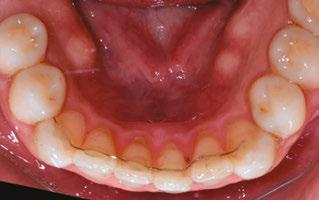

Figure 5: Final lower occlusal

The treatment spanned a total of 12 appointments, which included all routine, emergency, and one reposition appointment. Notably, the reposition was necessitated by a clinician error in the delivery of a bonding jig, resulting in bracket misplacement. This underscores the technique sensitivity involved in indirect bonding systems and highlights the importance of clinician training and procedural verification. Emphasis on consistent technique evaluation and training among providers has proven instrumental in reducing such avoidable errors (Figures 4-6).